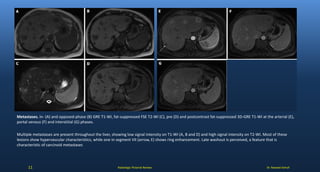

Metastases. In- (A) and opposed-phase (B) GRE T1-WI, fat-suppressed FSE T2-WI (C), pre (D) and postcontrast fat-suppressed 3D-GRE T1-WI at the arterial (E),

portal venous (F) and interstitial (G) phases.

Multiple metastases are present throughout the liver, showing low signal intensity on T1-WI (A, B and D) and high signal intensity on T2-WI. Most of these

lesions show hypervascular characteristics, while one in segment VII (arrow, E) shows ring enhancement. Late washout is perceived, a feature that is

characteristic of carcinoid metastases